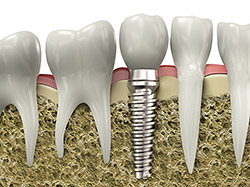

Implant Restoration

implantsIf you have missing teeth, it is crucial to replace them. Without all your teeth, chewing and eating can destabilize your bite and cause you discomfort. When teeth are missing, your mouth can shift and even cause your face to look older. Implants are a great way to replace your missing teeth, and if properly maintained, can last a lifetime!

An implant is a new tooth made of metal and porcelain that looks just like your natural tooth. It’s composed of two main parts: One part is the titanium implant body that takes the place of the missing root, and the second part is the tooth-colored crown that is cemented on top of the implant. With implant treatment, you can smile confidently knowing no one will ever suspect you have a replacement tooth.

In addition to tooth replacement, implants may be used to anchor dentures, especially lower dentures that tend to shift when you talk or chew. For patients with removable partial dentures, implants can replace missing teeth so you have a more natural-looking smile.